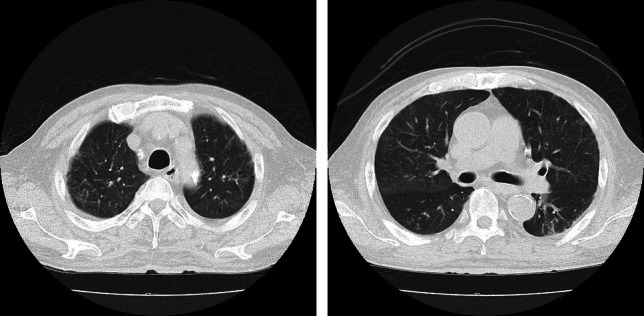

Seasonal influenza is prevalent globally, particularly during winter months. It is well documented that this disease causes severe, often fatal complications in hemodialysis patients. While numerous reports have focused on novel influenza viruses, there is a paucity of case reports detailing seasonal influenza viral infections in this patient population. This case presents a 71-year-old male undergoing hemodialysis who developed severe seasonal influenza A pneumonia despite receiving the influenza vaccine and early antiviral treatment. Initially presenting with fever, cough, and myalgia, the patient was diagnosed with influenza A virus infection and hospitalized due to heightened risk associated with dialysis and an elevated inflammatory response. Despite treatment with two different antiviral medications, his condition deteriorated, leading to ARDS (acute respiratory distress syndrome). The administration of steroid pulse therapy resulted in significant clinical improvement. This case underscores the severe nature of influenza virus-related illnesses in dialysis patients, even with vaccination and early antiviral intervention. It also suggests the potential benefit of early steroid pulse therapy in managing severe influenza pneumonia in high-risk individuals.